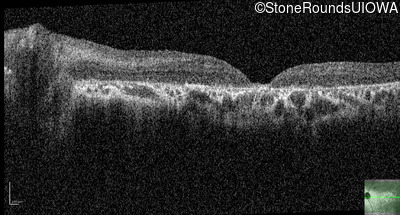

Optical Coherence Tomography - Right - 10/160 sc

Exemplar / OCT Stack